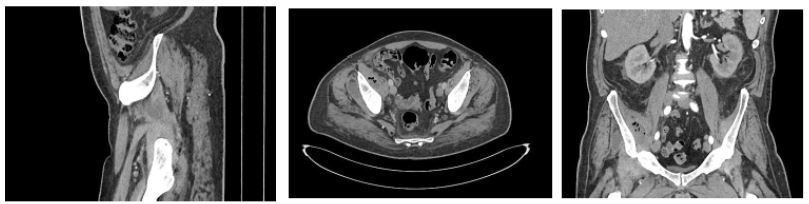

Before the fever began, he complained of anaemia, which developed prior to the onset of the fever. Despite being prescribed oral antibiotics, he experienced no improvement. He later developed progressive right anterior thigh pain and limping, treated with Relaxon and Panadol, but without relief. He now reports right ankle pain with similar symptoms, diagnosed as septic arthritis by MRI (Figure 1) and underwent drainage with persistent fever.

Figure 1: Left Ankle Septic Arthritis MRI.

- Evidence of Thick Peripherally Enhancing Effusion Involving the Talocrural and Subtalar Joint Spaces.

- Diffuse Subcutaneous Edema Seen Overlying the Lateral Malleolus Eith Extension into the Dorsal Aspect of the Hindfoot with No Well-Formed Collection Seen.

Septic Arthritis

The development of septic ankle arthritis in our case aligns with existing literature, which highlights brucellosis’s potential to cause significant joint involvement, including septic arthritis and osteoarthritis [12]. Early recognition and treatment are crucial to preventing joint damage and chronic complications. A report on septic arthritis caused by Brucella melitensis underscores the importance of maintaining a high suspicion for brucellosis in patients presenting with joint symptoms, particularly those with relevant exposure histories [13].